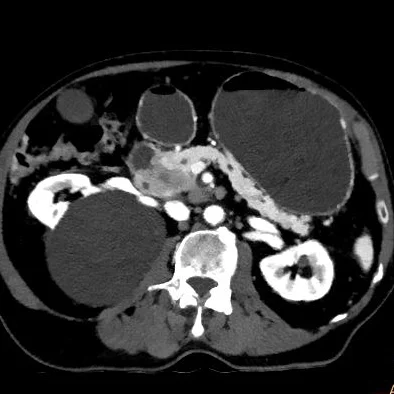

Pancreatic cancer

81 year old male with abdominal pain radiating to the back.

Pancreas mass spreading into the retroperitoneum better delineated on 45 keV image, the margin of the cancer is much easier to appreiate. Note dilated stomach from gastric outlet obstruciton.

Conventional CT, oblique axial